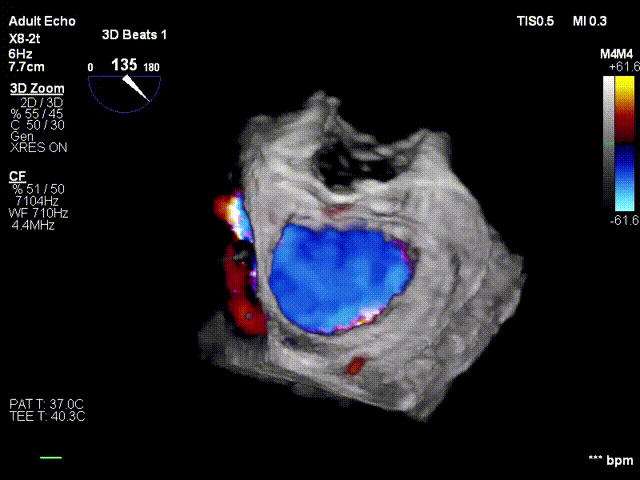

术前3D彩色

二尖瓣交界联合彩色

反流主要来源于2区累及1、3区